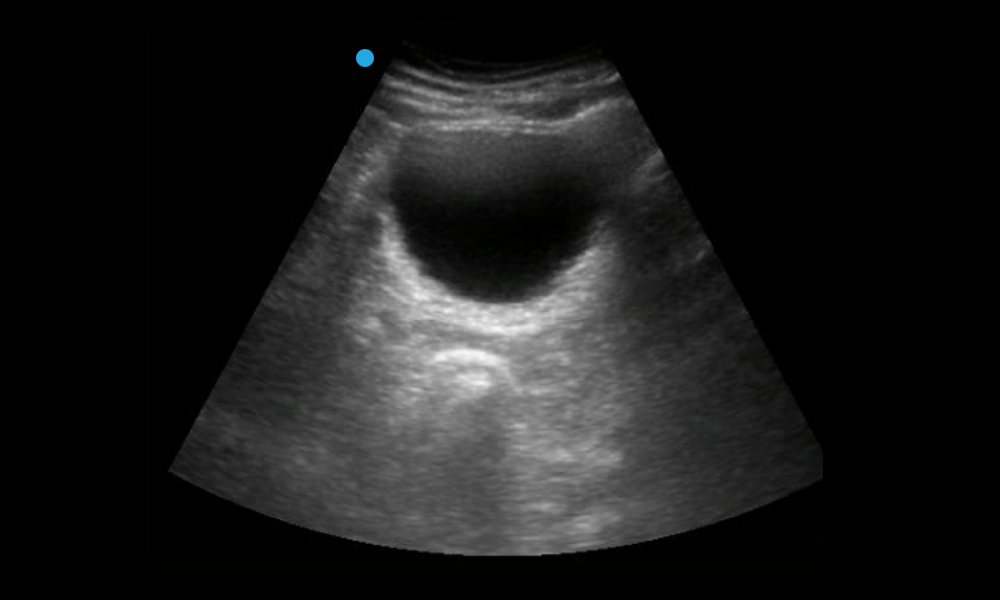

What is the anechoic structure?

Choose one

Ascites

Spleen

Bladder

Aorta